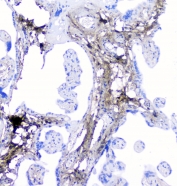

IHC staining of FFPE human placenta with LUM antibody at 1ug/ml. HIER: boil tissue sections in pH6, 10mM citrate buffer, for 10-20 min followed by cooling at RT for 20 min.